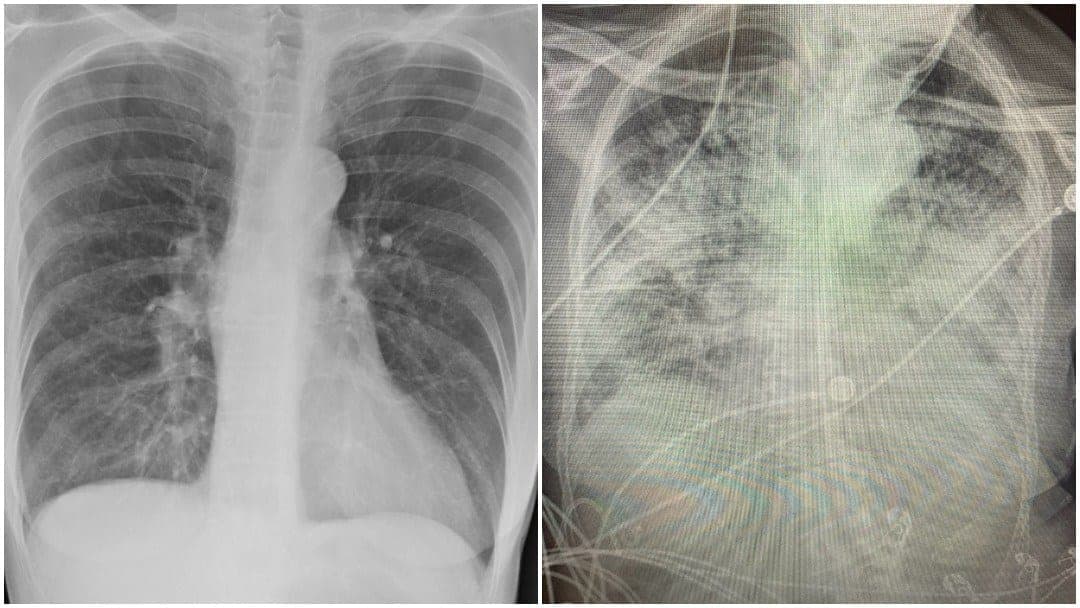

[caption id="attachment_165011" align="alignnone" width="660"]

Un nuevo estudio ha revelado que puede haber hasta 50 secuelas a largo plazo en los pacientes que han tenido Covid-19; ve cuáles son los más comunes[/caption]